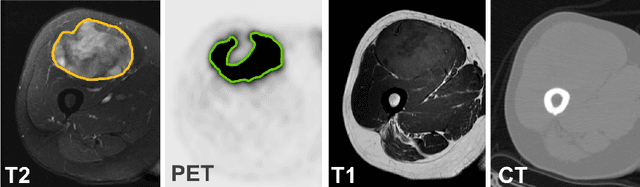

Abstract:Tumor segmentation in multimodal medical images has seen a growing trend towards deep learning based methods. Typically, studies dealing with this topic fuse multimodal image data to improve the tumor segmentation contour for a single imaging modality. However, they do not take into account that tumor characteristics are emphasized differently by each modality, which affects the tumor delineation. Thus, the tumor segmentation is modality- and task-dependent. This is especially the case for soft tissue sarcomas, where, due to necrotic tumor tissue, the segmentation differs vastly. Closing this gap, we develop a modalityspecific sarcoma segmentation model that utilizes multimodal image data to improve the tumor delineation on each individual modality. We propose a simultaneous co-segmentation method, which enables multimodal feature learning through modality-specific encoder and decoder branches, and the use of resource-effcient densely connected convolutional layers. We further conduct experiments to analyze how different input modalities and encoder-decoder fusion strategies affect the segmentation result. We demonstrate the effectiveness of our approach on public soft tissue sarcoma data, which comprises MRI (T1 and T2 sequence) and PET/CT scans. The results show that our multimodal co-segmentation model provides better modality-specific tumor segmentation than models using only the PET or MRI (T1 and T2) scan as input.